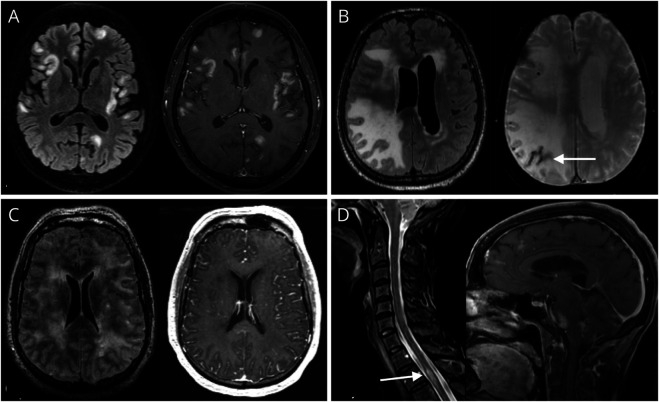

Results: Twenty-six patients (50% female) met the study criteria, including 7 with amyloid-beta-related angiitis (ABRA). The median age at onset was 55.5 years (range 20-82), and headache (76.9%) and altered mental status (61.5%) were common presenting symptoms. Neuroimaging commonly showed bihemispheric T2/FLAIR lesions (77%) and abnormal gadolinium enhancement (88.5%), but intracranial vascular irregularities indicating large or medium vessel involvement were rare (11.5%). Among patients with non-ABRA sv-PCNSV (n = 19), some demonstrated spinal cord involvement (15.8%) and others exhibited isolated unihemispheric disease (21.1%). Although CSF testing (n = 23) often demonstrated mild pleocytosis, a notable minority of patients (17.4%) had a normal CSF analysis. Six patients (23.1%) underwent repeat brain biopsy because of initial nondiagnostic findings. Remission was achieved in all patients in the EIT group (n = 12/12), in contrast to 78.6% of patients in the ESC group (n = 11/14). Time to remission was significantly shorter among patients in the EIT group compared with the ESC group (median 5 vs 19 months, hazard ratio = 0.24, 95% CI [0.10-0.63], p < 0.005). Most patients achieving remission continued maintenance therapy, with an overall relapse rate of 19%.